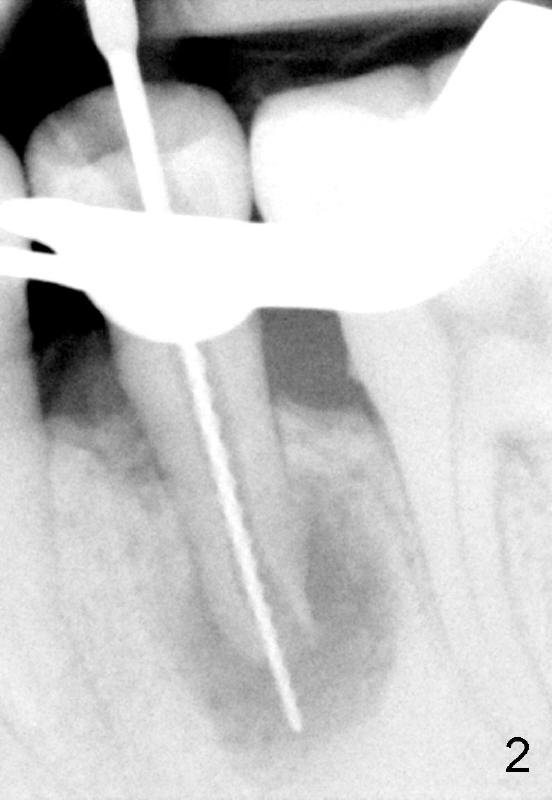

A 40-year-old Chinese man has periodic (once a month) mild pain and swelling in the lower left quadrant. Clinical exam reveals dens evaginatus (Fgi.1': <) in #20. Upon pressure from mouth mirror handle, there is limited amount of purulent discharge from the fistula (Fig.1": <). Preop PA shows a large canal with large periapical radiolucency (Fig.1). RCT started on Aug 6, 2010 with #70 file at 20 mm (Fig.2), #120 file at 16 mm (Fig.3) and CaOH paste in the canal (Fig.4). The dressing changed on Oct 8, 2010 (Fig.5). RCT finished on Jan 25, 2011 with master cone (rolled with several gutta perchae) (Fig.6), lateral condensation (Fig.7) and after vertical condensation and build-up (Fig.8). The canal was wet in the last two appointments with no sign of apexification. Follow up is done in 7 months (Fig.9), 11 months (Fig.10) and 18 months. Although the patient reports no pain after the treatment, the fistula remains with purulent discharge. The patient does not accept apical surgery. What should we do? Retreat with MTA (1,2,3)?